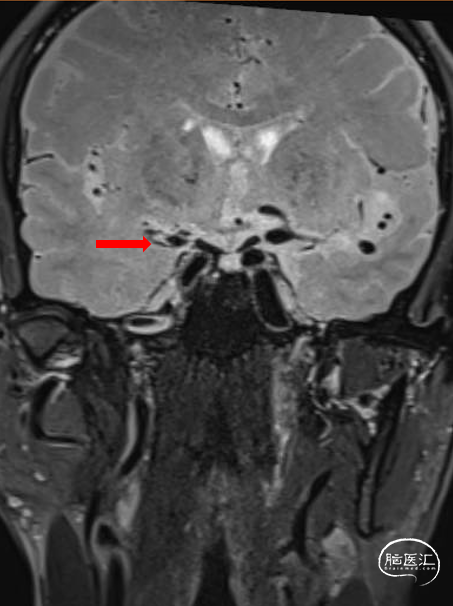

颅脑斑块分析:右侧大脑中动脉M1-3段混合斑块形成(易损斑块及少许血栓附着),管腔重度狭窄。

T1增强

T2

斑块分析:左侧大脑中动脉近中段M1段重度狭窄、M1远段-M2分支起始处混合斑块形成,局部管腔闭塞;远端分支较对侧明显减少。

T2

T1增强